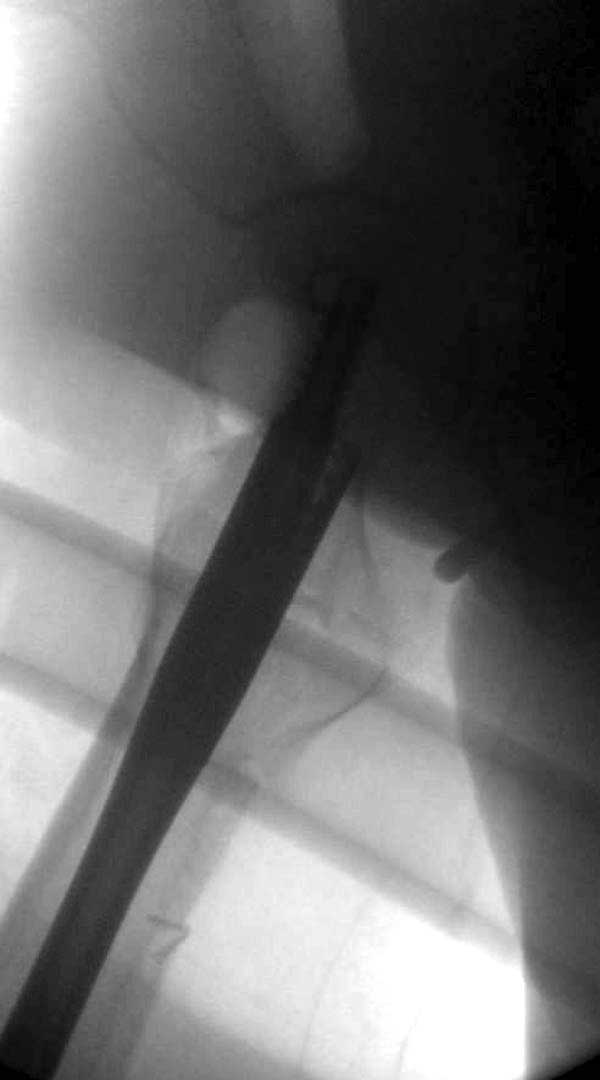

Вторая операция- это фаза сохранения головки бедра. Желательно приложить все усилия и сохранить головку, но, как видно, “фиаско” продолжается. Здесь вместо нейтрализации сил между медиальной и латеральными сторонами была попытка удержать варус. Варус не удержать ни деротационными шурупами о котором говорили и не костными стружками вбитые в шейку, потому что вся нагрузка упирается в головку.

Как отметил Евгений, 95 degree Blade Plate Fixed Angle device  расчитана на восстановление взаимоотношении между головкой и диафизом, а все остальные фиксаторы (Gamma, Afifuxus и др.) работают за счет нагрузки в верхнем полюсе головки. Верхний полюс успели разрушить, и в головке единственное место, который смог бы удержать широкий клинок конструкции, это медиально-низкий сегмент. После установки клинка засчет дистракции можно удлинить конечность на 15мм, а добавленный в дефект ауто-графт закончил бы дело.